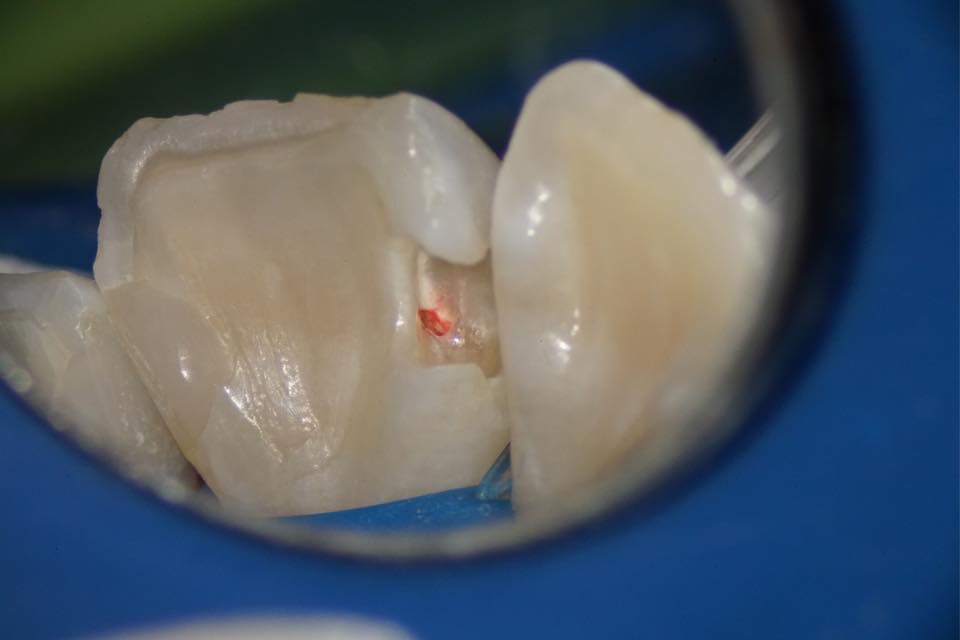

抜髄、歯の中の神経をすべて取り除く治療の事を抜髄と言います。

標準的な診査診断では、歯の神経、歯髄に少しでも感染があると、全ての神経をとることが標準的な治療です。

しかし近年、マイクロスコープ、バイオセラミック系材料、歯科接着などが出て来て、従来では不可能であった事が、出来る可能性がある時代に入って来ました。歯の神経、歯髄は可能であれば、出来るだけ歯髄を残す事が歯にとって、とても良い事です。

歯髄を残すという事は、歯の血液供給など歯の栄養源が保たれる事です。歯髄の感染は、どこまで感染しているかは、経験的なイメージしかまだわかっていない為、確実に歯髄を残せる、残せないの診断が術前に行うことが出来ません。

治療中の神経、歯髄の状態、色や毛細血管が確認できるとか、根管内壁に生着しているなどの臨床写真で判断しています。

また、成功例としては自発痛(何もしてなくても痛い)、打診痛(叩いて痛い)の症状があると虫歯の進行が歯髄まで感染してると診断され、抜髄の診断でしたが、海外の先生達の症例で成人でも断髄(一部分の神経だけを取り除き、残りの神経、歯髄は残す)治療を観てきたので、患者さんに急に痛くなる可能性がある事を伝えて、同意を得て神経の保護、一部分の神経、歯髄を取り除き、残りの歯髄を残す治療を2014年から実践しています。

小児歯科の分野では、断髄処置は、大学レベルでも行われていますが、成人では断髄処置は禁忌であると教えられてます。まだ不確かな事もかなりある為、アメリカとヨーロッパでも考え方が違い、自分の臨床経験が一番の頼りだと考えています。

この写真は、感染部を削合して行ったら、神経、歯髄が露出したためバイオセラミックで神経、歯髄を保護している写真です。